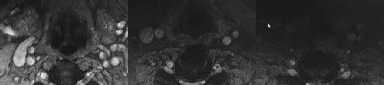

CLINICAL SITUATION

Figures 1 and 2 are the sagittal and axial MRI images at the L4-5 level from a patient with intractable left leg pain, paresthesias, and weakness of grade 3

of 5. Physical therapy has failed, and the patient feels he is becoming progressively weaker.

Which nerve root is being affected?

Discussion: C

The MRI images show a left L4-5 posterolateral disk herniation compressing the left L5 nerve root. Posterolateral disk herniations in the lumbar spine affect the traversing nerve roots; therefore, at the L4-5 level, the traversing L5 nerve would be affected. Far-lateral disk herniations in the lumbar spine affect the exiting nerve roots, so a far-lateral herniation at L5-S1 would affect the L5 nerve root also. The motor innervation for the lumbar nerve roots are L2: hip flexion, L3: knee extension, L4: ankle dorsiflexion, L5: long toe extension, and S1: ankle plantar flexion. The sensory innervation for the lumbar nerve roots are L3: medial thigh, L4: anterolateral thigh and medial calf, L5: anterolateral calf, and S1: lateral foot. Nonsurgical treatment, including medications and physical therapy, has failed, and the patient has noticed a progressive deficit confirmed by weakness of grade 3 of 5 on examination. Surgery is indicated because of the patient’s progressive weakness and the failure of nonsurgical care. A fusion is not indicated without evidence of instability.